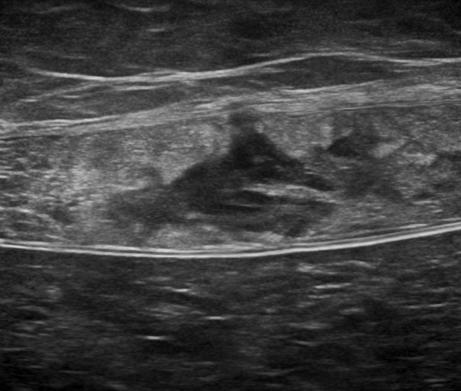

Chấn thương thành bụng - Ảnh 4

Chấn thương thành bụng

» Thông tin: Nam giới – 50 tuổi.

» Lâm sàng: Chấn thương thành bụng.

# Đụng dập, tụ máu cơ thành bụng.